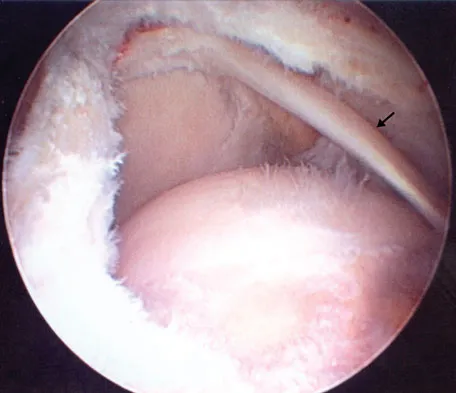

Question 68

Figure 43 shows an arthroscopic view of a right shoulder through a lateral portal in the beach chair position. The arrow is pointing to what structure?

Explanation